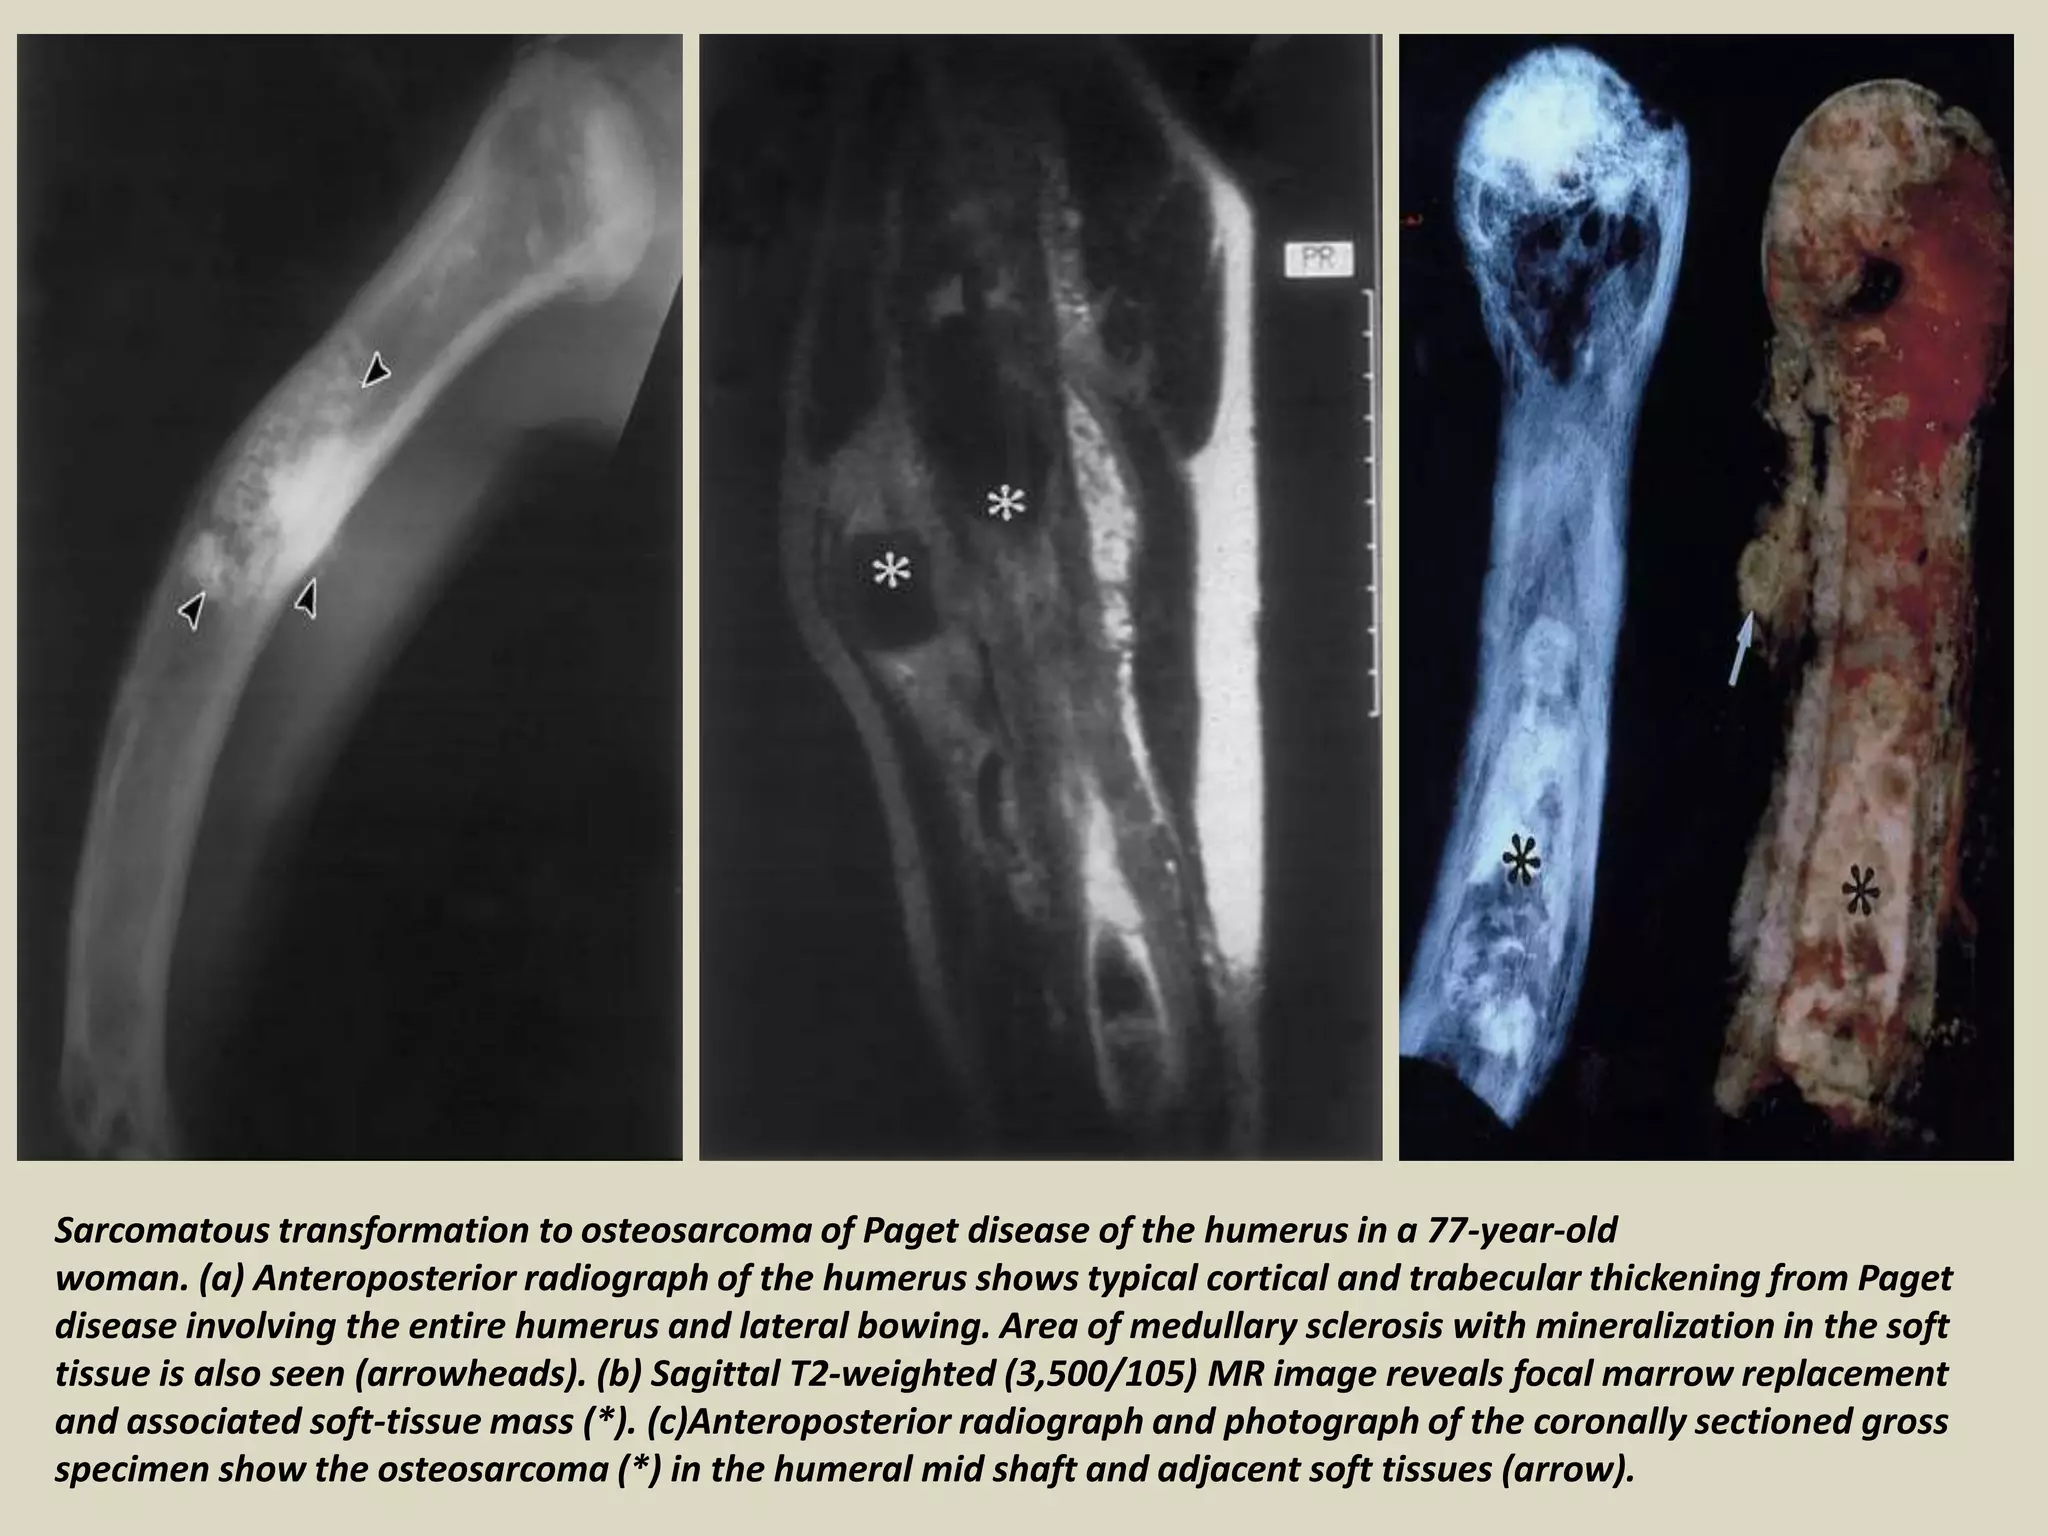

Sarcomatous transformation to osteosarcoma of Paget disease of the humerus in a 77-year-old

woman. (a) Anteroposterior radiograph of the humerus shows typical cortical and trabecular thickening from Paget

disease involving the entire humerus and lateral bowing. Area of medullary sclerosis with mineralization in the soft

tissue is also seen (arrowheads). (b) Sagittal T2-weighted (3,500/105) MR image reveals focal marrow replacement

and associated soft-tissue mass (*). (c)Anteroposterior radiograph and photograph of the coronally sectioned gross

specimen show the osteosarcoma (*) in the humeral mid shaft and adjacent soft tissues (arrow).